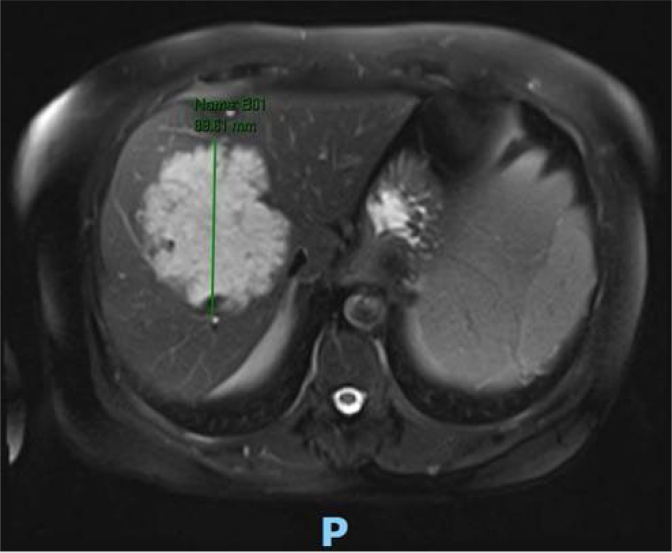

In patients with synchronic liver colorectal metastasis, resection of the primary tumor and liver metastases is the only potentially curative strategy. In such cases, there is no consensus on whether resection of the primary tumor and metastases should be performed simultaneously or whether a staged approach should be performed (resection of the primary tumor and after, hepatectomy, or hepatectomy first). Patients with no bowel occlusion and with extensive liver disease are advised neoadjuvant oncological therapy. Similarly, various strategies such as portal vein embolization, liver deprivation, two-staged hepatectomy, and associating liver partition and portal vein ligation are available for patients who do not have a sufficient future liver remnant (generally 30-40% of the total). Therefore, a multidisciplinary approach is required for the treatment of these patients.